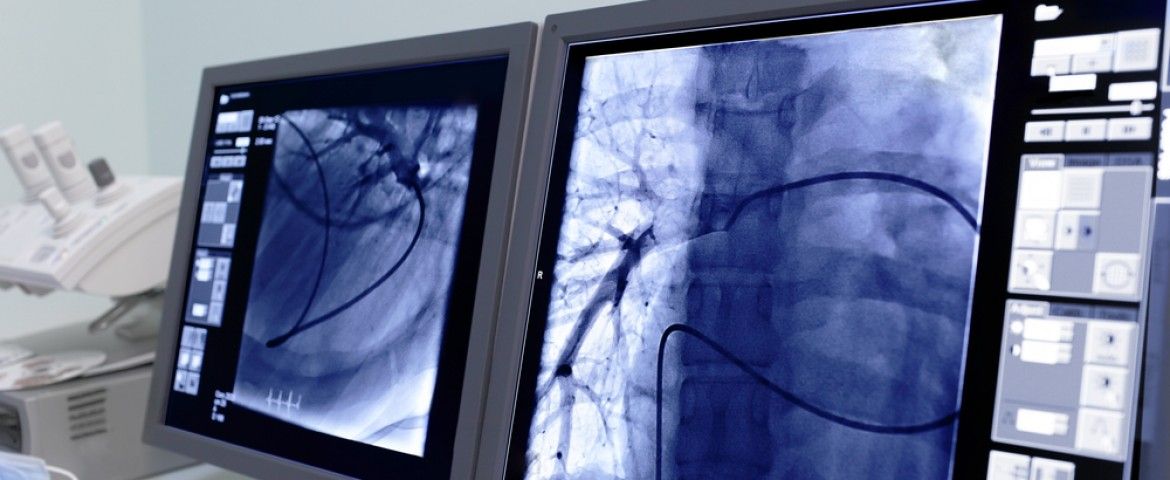

Коронарография - это золотой стандарт в исследование артерий сердца, которое выполняют для того чтобы изучить анатомию коронарных артерий, посмотреть проходимость, выявить наличие сужений или тромбов, и принять решение как лечить кардиологического пациента. Выполняют коронарографию при ишемической болезни сердца, подозрении на острый инфаркт миокарда, наушениях ритма. Проводится коронарография в рентгенхирургической лаборатории, под местной анестезией путем прокола в руке, хирург вводит контраст в специальные катетеры и записывает видео в разных проекции для оценки артерий сердца. Через 2 часа после исследования через руку, пациент уже может ходить. Коронарогафия - малотравматичная, безопасная и очень важная диагностика артерий сердца, осложнения при которой случаются крайне редко.